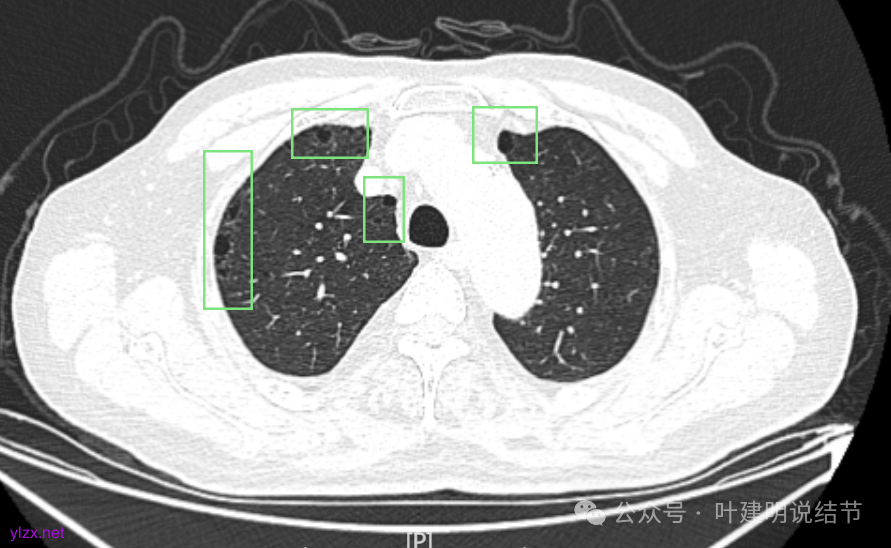

两肺其他地方多处肺大泡。

再看2023年时的影像主要层面:

左上当时也有,但囊壁明显是较现在薄的。